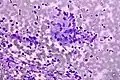

Micrografía de una tinción de Field que muestra melanoma maligno.